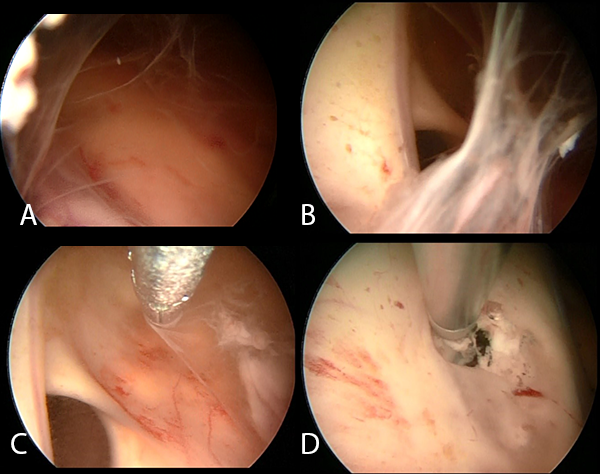

Se realizó la neuroendoscopía utilizando una óptica de 0 grados, de 30 cm. ingresando por el lóbulo frontal derecho. Inmediatamente al ingreso de la óptica se evidenciaron múltiples adherencias intra ventriculares. El foramen de Monro se encontraba parcialmente obstruido por una adherencia, además el epéndimo presentaba coloración amarillenta y las adherencias se encontraban difusamente en los ventrículos. Se intentó realizar una extracción de las membranas, pero se encontraban adheridas firmemente a las paredes ventriculares. (Imagen 4). Se realizó la fenestración del Septum Pellúcidum, con colocación de una nueva DVE, por lo que el paciente presentó mejoría clínica e imagenológica (Imagen 5).

Imagen 4: Fotografías intraoperatorias endoscópicas del ventrículo derecho. (A).Múltiples adherencias intraventriculares con epéndimo ligeramente amarillento. (B) Se evidencia obstrucción parcial del foramen de Monro. (C) Se realiza la extracción parcial de membranas intraventriculares. (D) Realización de la fenestración del Septum Pellucidum. Se evidencia ligero punteado en el epéndimo. SP: Septum Pellucidum; VSA: Vena septal anterior; FM: foramen de Monro; FO: fórnix.

La hidrocefalia en pacientes con TBC meníngea es más común de tipo comunicante (aproximadamente el 80%).(11) En el caso del paciente, probablemente las adherencias intraventriculares y la obliteración parcial del foramen de Monro hayan causado una hidrocefalia asimétrica y obstructiva.

Torrez-Corzo et al.(12) realizaron 24 endoscopías ventriculares a pacientes con meningitis, reportando que dichos pacientes presentaron aracnoiditis adhesiva, que incluso cubrían nervios craneales. Los hallazgos endoscópicos en nuestro paciente fueron similares, ya que se evidenciaron múltiples adherencias.